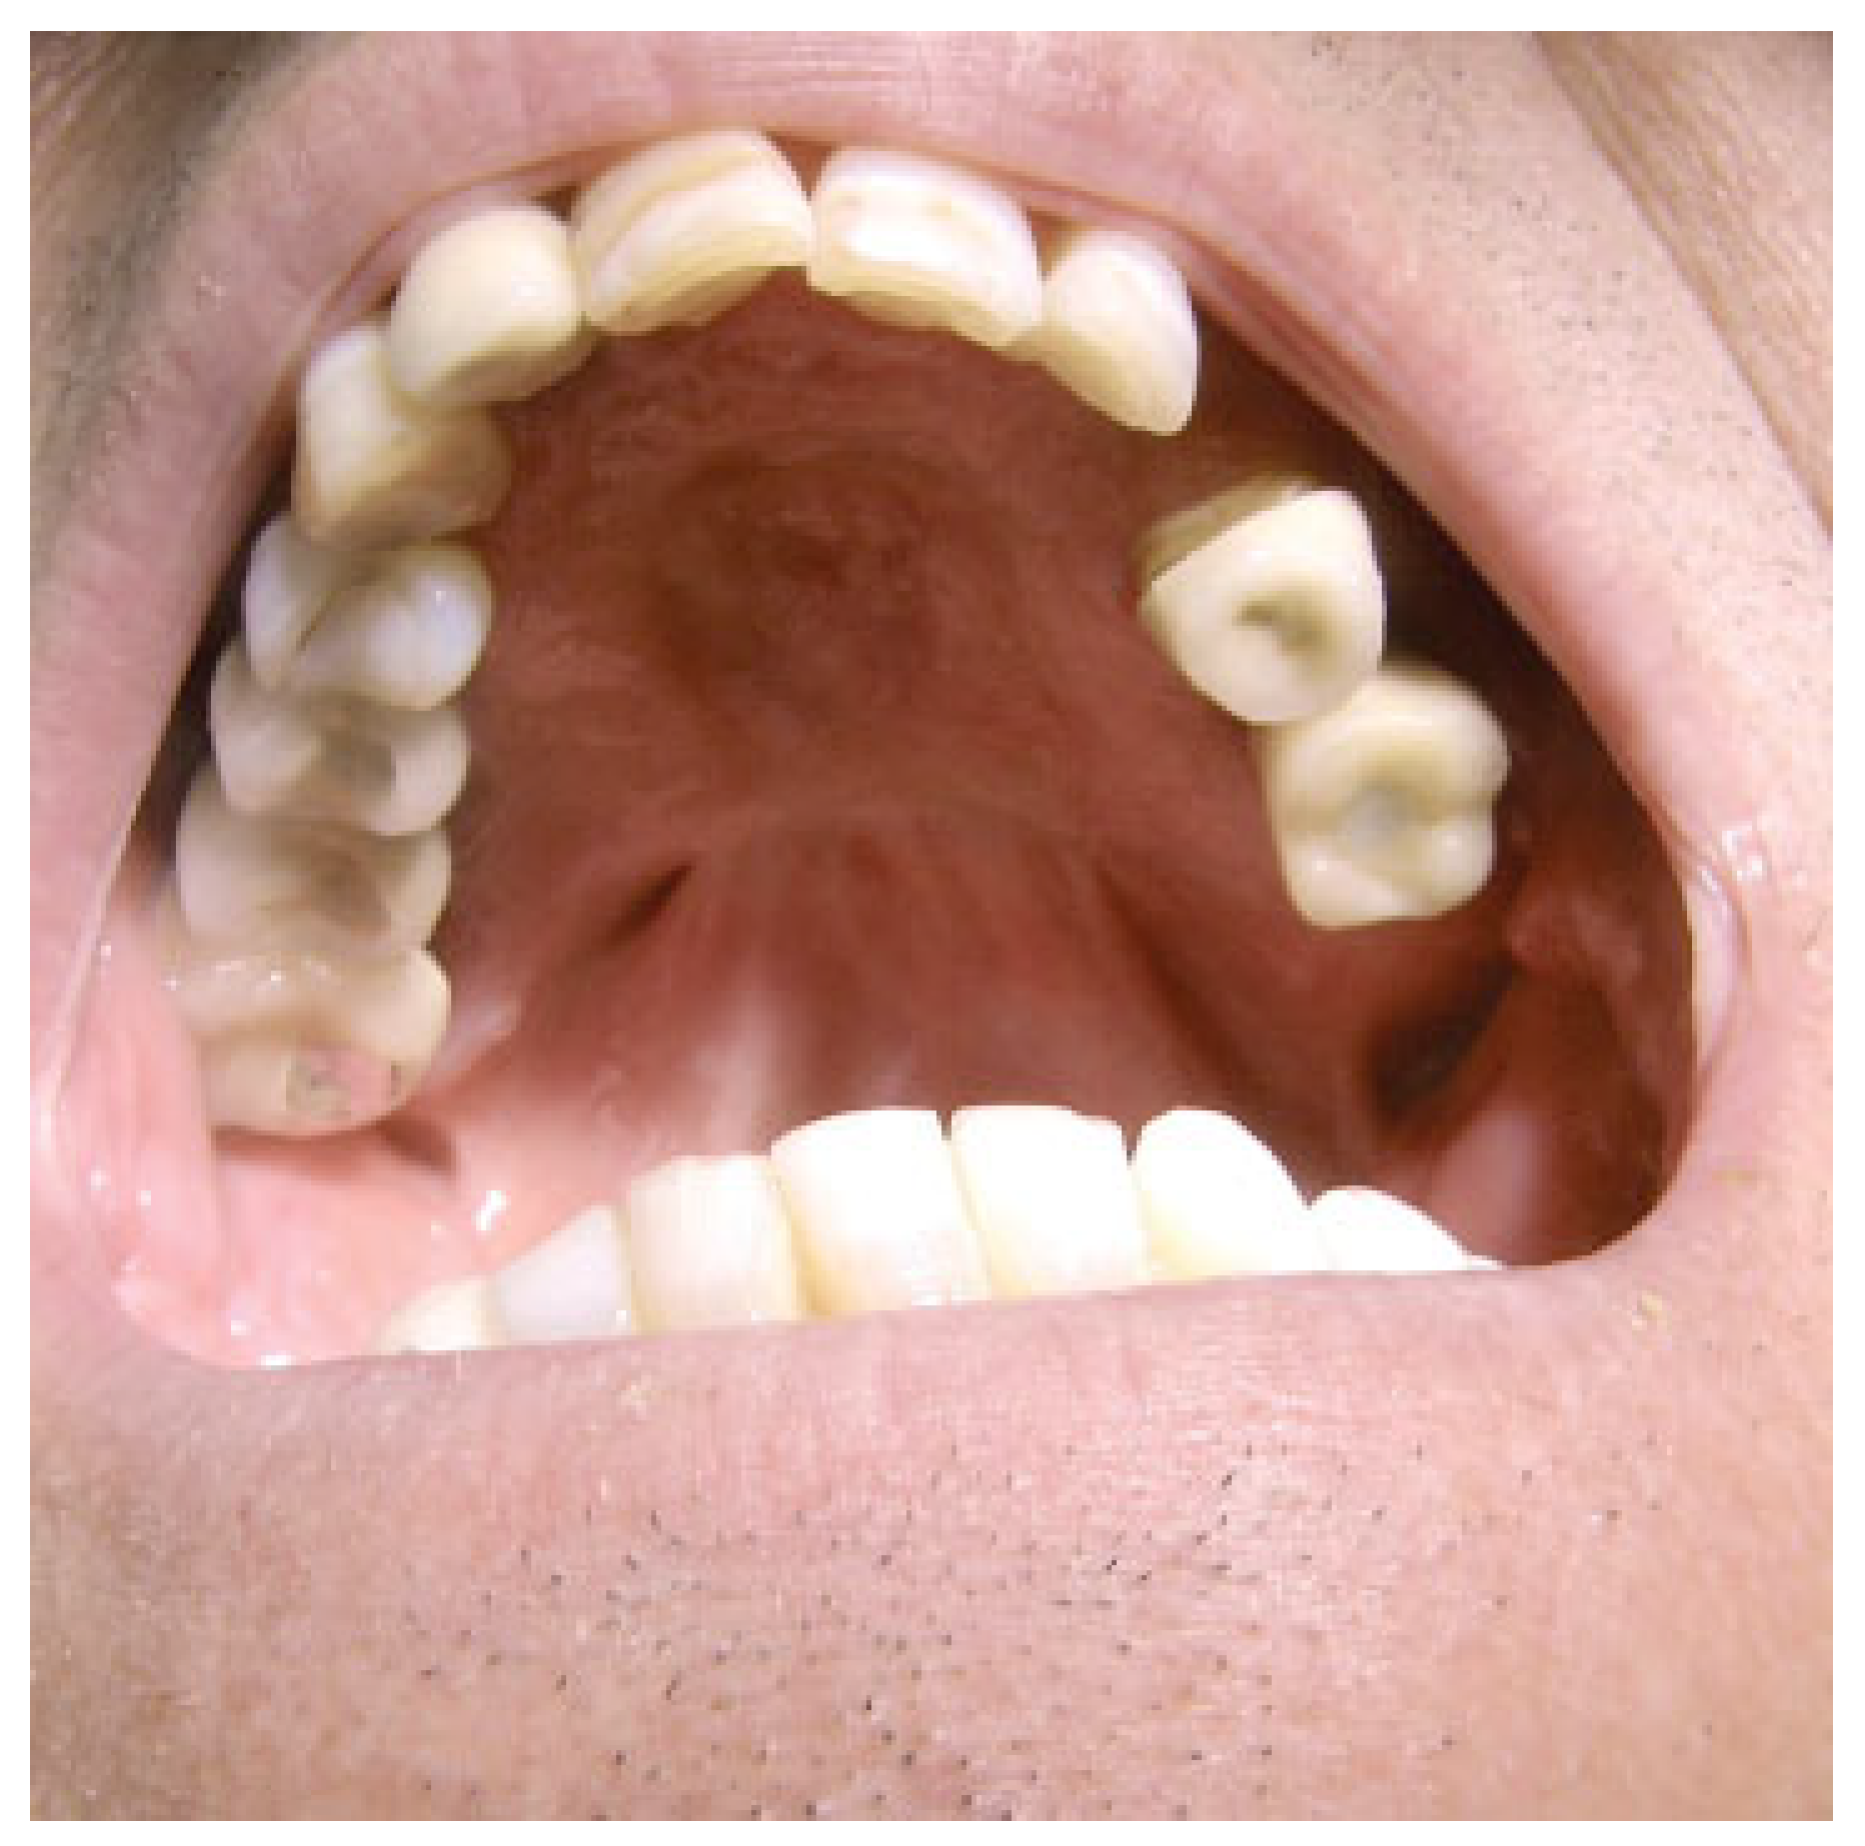

We have applied this approach in five patients with squamous carcinoma of the palate accomplishing free surgical margins in all cases. However, two of these five patients required adjuvant radiation therapy (RT) in basis of the tumor size. Among the complications, one patient developed dehiscence of the muscle suture, probably in relation with his poor nutrition condition and needed a second surgical procedure 1 week later. No infections or cerebrospinal fluid leaks were demonstrated in any patient. With the exception of the patient with the muscle dehiscence, all the patients were discharged from the hospital within the first week, achieving good functional and aesthetic results in all cases. Initial muscle bulky inside the oral cavity may be present, but it is progressively decreased during the next months with the gradual atrophy process of the muscle (Figure 8 and Figure 9).

Figure 9. Postoperative view 1 year after the surgery. Gradual muscle atrophy and metaplasia determine the final result mimicking the normal palatine mucosa.